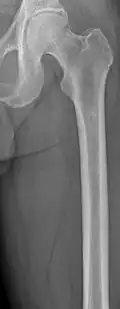

-

Femur with multiple myeloma lesions -

Same femur before myeloma lesions for comparison -